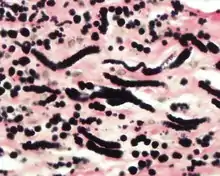

By microscopie view, there is an admixture of heavy dense bands of collagenous tissue dissected by fat and abnormal elastic fibers. The elastic fibers are often quite large and are easily identified. The elastic fibers are coarse, thick, and darkly eosinophilic, often fragmented into globules, creating a "string of pearls" or "pipe cleaner" appearance. Because of degeneration, the elastic fibers will appear as globules with a serrated or "prickled" edge.[4]

Histochemistry

The elastic fibers will be highlighted by a Weigert or von Gieson elastic stains.[8]